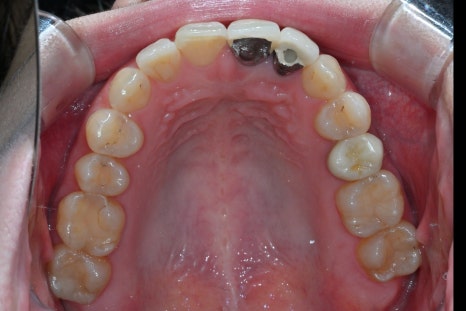

At the first visit

The patient’s existing crown had become discolored,

and the border with the gums was not natural,

so she was always conscious of it in daily conversations

- Rechecking the tooth condition after removing the existing crown

To resolve discoloration and border issues, the existing restoration was removed,

and the gum line and tooth shape were newly designed.